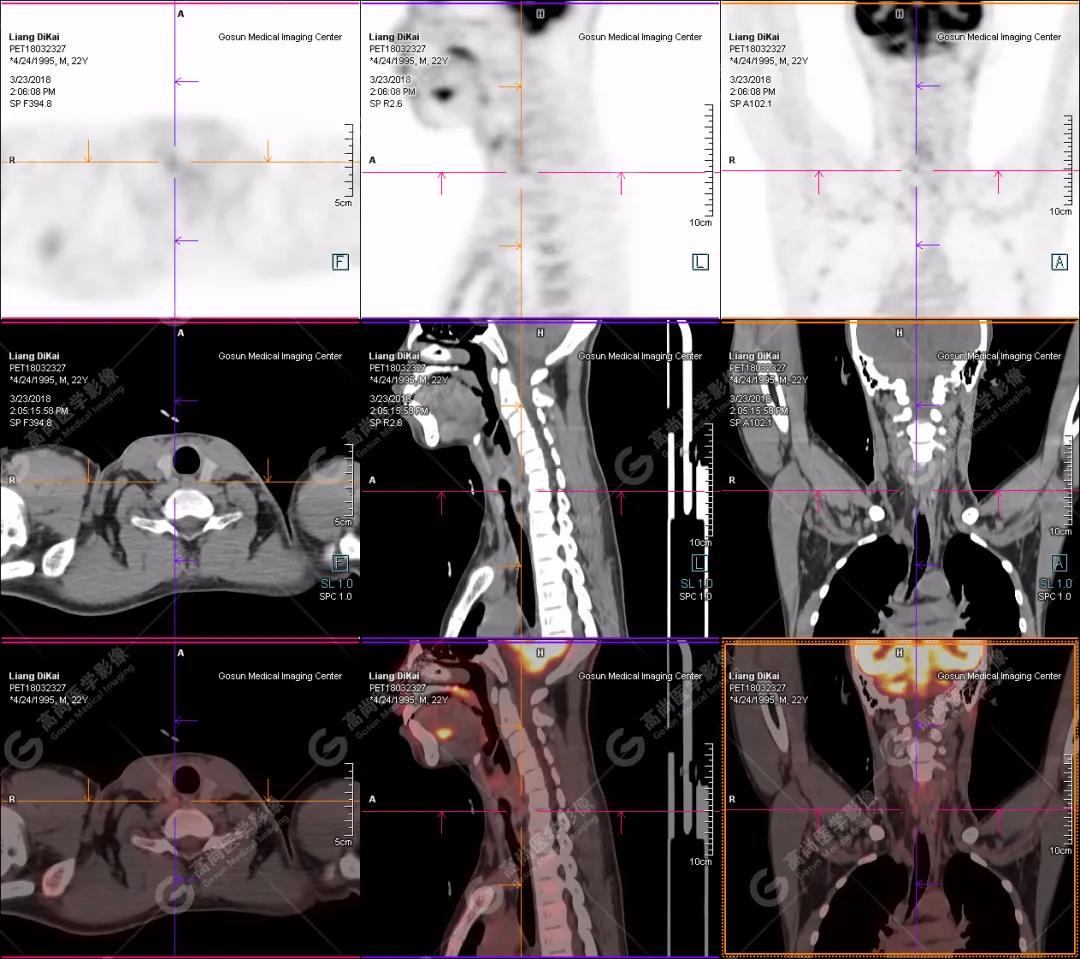

1.右肘關(guān)節(jié)周圍、骶尾部皮下、雙側(cè)臀部、盆腔左側(cè)壁及左側(cè)大腿根部肌肉、肌間隙多發(fā)結(jié)節(jié)狀、片塊狀及不規(guī)則巨塊狀高密度鈣化灶,伴代謝不均勻輕度增高,考慮為鈣質(zhì)沉著癥;

2.甲狀腺雙葉后方多發(fā)(右2個,左1個)小結(jié)節(jié)狀軟組織影,部分代謝輕度增高,多考慮為甲狀旁腺腺瘤。